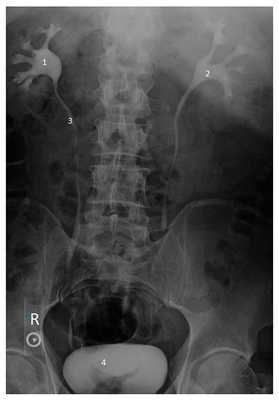

Рисунок. Экскреторная урография. 1 и 2 - чашечно-лоханочная система правой и левой почки, 3 - мочеточник, 4 - мочевой пузырь.